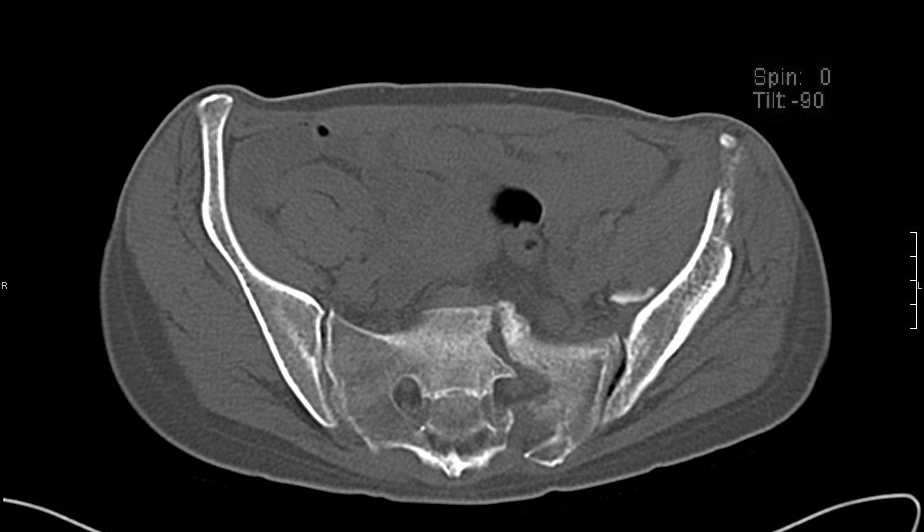

Больная 43 года (промышленный альпинист), 28.07.08 в результате падения с 5 этажа получила политравму: Перелом свода и основания черепа. Вертикально-нестабильное повреждение таза, осложнённое разрывом мочевого пузыря. Чрезвертельный перелом левого бедра. Перелом правой таранной кости, переломовывих правой кубовидной кости. Тупая травма живота, разрыв печени, ушиб почек. Забрюшинная гематома. В день травмы - лапаротомия, ушивание ран печени. Разрыв мочевого пузыря не диагностирован. Течение болезни осложнилось развитием мочевого затёка и обширной пред- и забрюшинной флегмоны, сформировался свищ мочевого пузыря. 19.8.2008 вскрытие, дренировние флегмоны, ревизия мочевого пузыря, обтурация мочевого свища (свищ закрылся в октябре), 1.10.2008 некрэктомия, пластика по Шеде-Лидскому правой кубовидной кости. По результатам КТ диагностирован рак правой почки (диагностическая находка), 8.10.2008 нефрэктомия справа. Переломы велись консервативно. Имеется вертикальное смещение левой половины таза с выраженным отведением крыла (клинически подвижности нет), несросшийся низкий двухколонный перелом левой вертлужной впадины с потерей конгруэнтности, укорочение около5 см, застарелый разрыв лонного сочленения, неправильно сросшиеся переломы обеих ветвей правой лонной кости с укорочением, патологическая подвижность лоно-седалищного фрагмента слева. Правая нижняя конечность неопорна, несмотря на то, что лежа прямую ногу поднимает, ходит на левой ноге (ортопедическая обувь) с костылями, справа тазобедренный ортез. Седалищные нервы работают.Урологи отпустили больную на 6 мес.

Мучаемся мыслями - как все это заставить ходить.Возможно ли первичное протезирование если просто синтезировать лонное сочленение с цементом и ванкомицином? Если делать большую реконструкцию, то с чего начать? Изрубить крыло и заполнить дефекты? Перерубить боковую массу и попытаться развернуть крыло обратно? Ждать год после закрытия свищей?